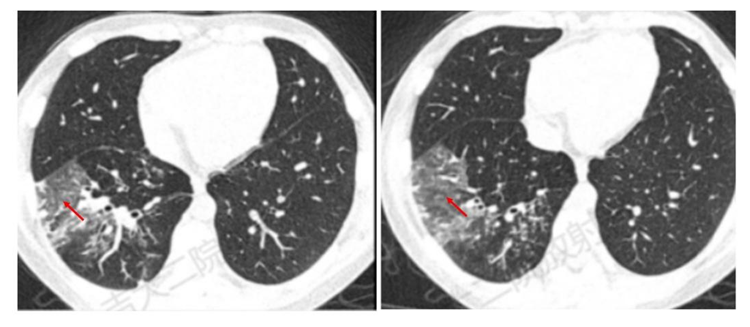

影像学检查尤其是CT是重要的检查手段,也是临床判断病情严重程度和评估预后的主要依据之一。支原体肺炎病理变化是首先侵犯气道粘膜上皮,引起支气管壁水肿增厚,接着向气道周围间质蔓延,引起肺间质充血、水肿及炎性细胞浸润,最后延伸至肺泡。在CT图像上主要有以下几种表现:

4.磨玻璃影:间质内水肿或部分肺泡内渗出,表现为磨玻璃样影。

5.大片实变:表现为中-高密度阴影,可有支气管气象,可伴有肺不张及胸腔积液,早期可表现为小叶中心结节影,随着病灶进展,进展为全小叶或更大范围。

随诊疾病的不同阶段,多种形态、大小不等和密度不均的病灶可混合出现,支气管壁增厚、树芽征、树雾征及实变影等征象可同时存在,结合咳嗽、发热等症状,可对支原体肺炎做出诊断。

肺炎支原体肺炎病灶可先后出现,此起彼伏,临床与影像不同步,往往表现为临床轻、影像重,而且在发病初期支原体抗体阴性或浓度不高,此时也不能排除支原体感染,所以CT在支原体肺炎诊断及评价治疗效果非常重要。